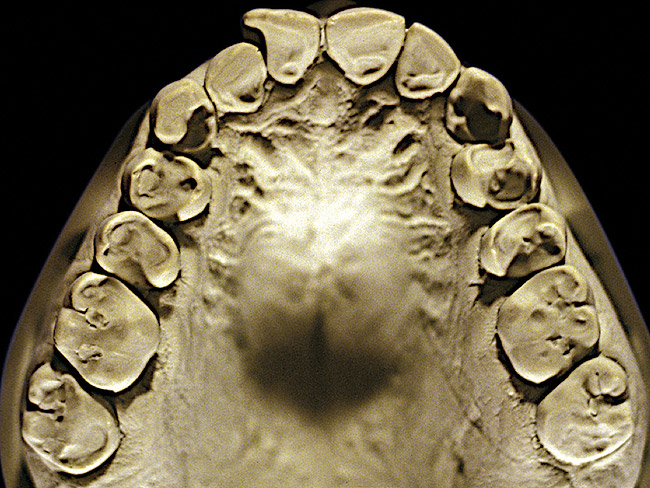

Figure 4  Advanced NCLTS from bruxism, maxillary arch.

Figure 4

The patient shown in Figure 3 and Figure 4 exhibited severe NCLTS from bruxism. Examination of the casts indicated that the NCLTS was progressively greater toward the anterior teeth. Cupping and cratering was not present because there was no secondary cause. Figure 5 and Figure 6 detail another bruxism patient, but to a lesser degree and one with cupping/cratering caused by toothpaste. The cups or craters were not caused from bruxism because the teeth could not touch the bottom of the invaginations. In both featured patients, upon hand-articulating the casts, the NCLTS facets matched up and the diagnosis of bruxism was confirmed.